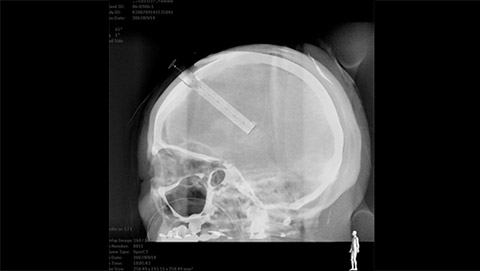

AlluraClarity motion compensation corrects for subtraction artifacts, automatically and in real-time. This is particularly important when placing small devices at the base of the skull.

2D navigation with Roadmap Pro is supported by automatic, real-time motion compensation and decreased subtraction artifacts. Clinical modes are optimized for various clinical applications.